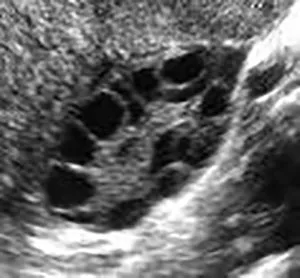

Polycystic ovary syndrome (PCOS) is a common reproductive endocrine disorder characterized by ovulatory dysfunction, excess androgen hormone levels, and polycystic appearing ovaries on ultrasound.

Black and white ultrasound image showing multiple dark, round cysts clustered within ovarian tissue, suggestive of polycystic ovary syndrome (PCOS).